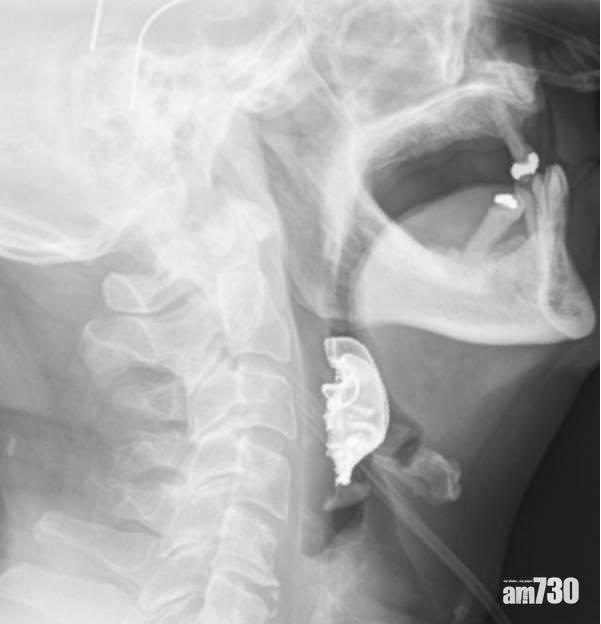

醫生為老翁照X光時發現喉嚨有異物。(互聯網)

英國醫學期刊(British Medical Journal)前日刊出一宗罕有個案,一名72歲老翁早前為移除腹部硬塊而接受手術,但手術後喉嚨感到痛楚、咳出血、吞嚥困難,於是回到醫院求醫,醫生未有發現任何問題,只提供了抗生素、類固醇及嗽口水。老翁其後情況惡化,再度入院,醫生懷疑他嚴重肺炎並為他照X光,終發現一副假牙卡在他的喉嚨內,相信是8日前的手術時滑落至喉嚨。假牙附近的組織出現腫脹及水泡,需做手術取出。其後事主因動脈撕裂而不停出血,接受了另一次緊急手術,6周後才康復。撰寫報告的專家呼籲,醫生及醫護人員必須在手術前後確認病人是否有戴假牙。